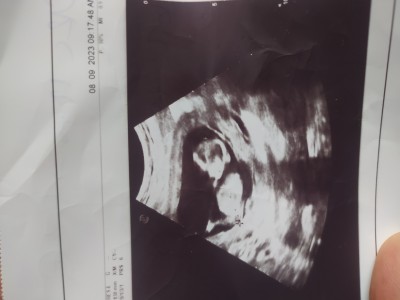

Burda 13+2 günlük doktorum hiç bir tahmin yapmadı devlete giriyom size sormak istedim bı tahmin yapabilirmisinz

Gebelik haftası 13+6